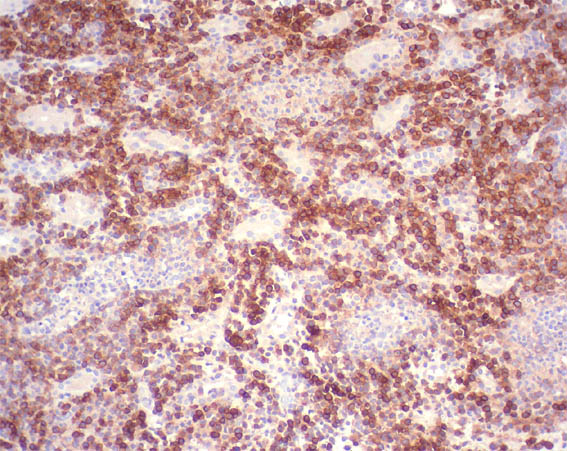

Figure 12. Immunohistochemistry for CD20, X200.

Figure 13. Immunohistochemistry for CD79a, X200.